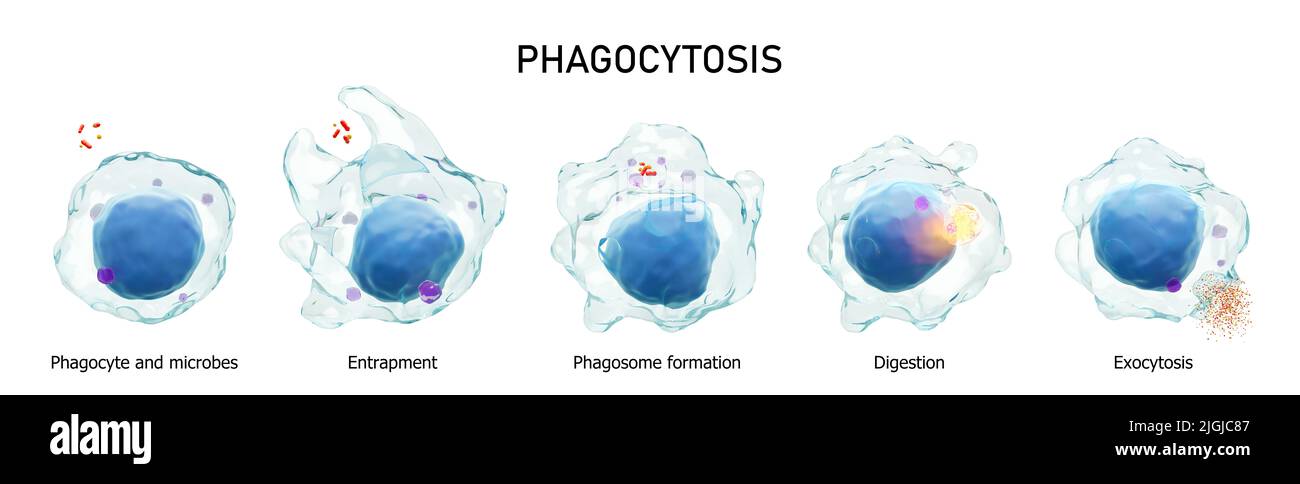

RF2JGJC84–Fagocitosi . Il processo graduale del macrofago è la deglutizione e l'uccisione di microbi. Fondo bianco isolato . Immunità medica concetto . 3D rende

RF2JGJC87–Fagocitosi . Il processo graduale del macrofago è la deglutizione e l'uccisione di microbi. Fondo bianco isolato . Immunità medica concetto . 3D rende